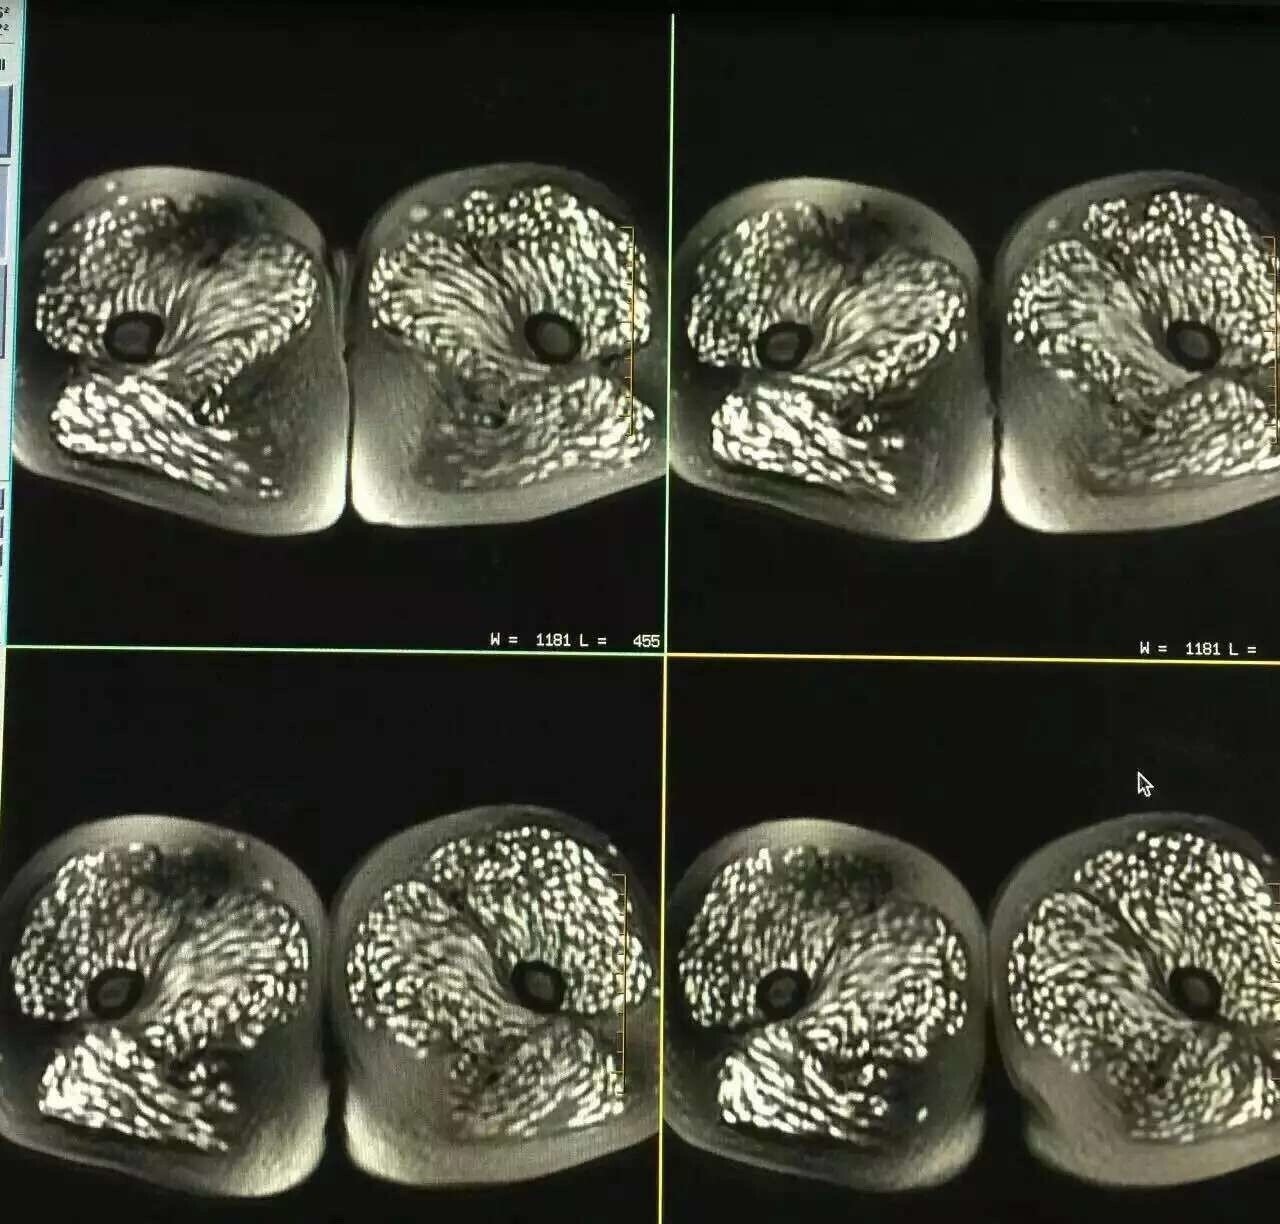

온 몸에서 통증이 느껴져 병원을 찾아가서 엑스레이 사진을 찍었는데

충격적이게도 온 몸에 기생충이 들끓고 있었다.

이 여성의 병명은 ‘낭미충증’이라는 것으로

사람의 소장에 기생하는 ‘유구조충’이라는 기생충의 알에 의해 일어나는 감염증이라고 한다.